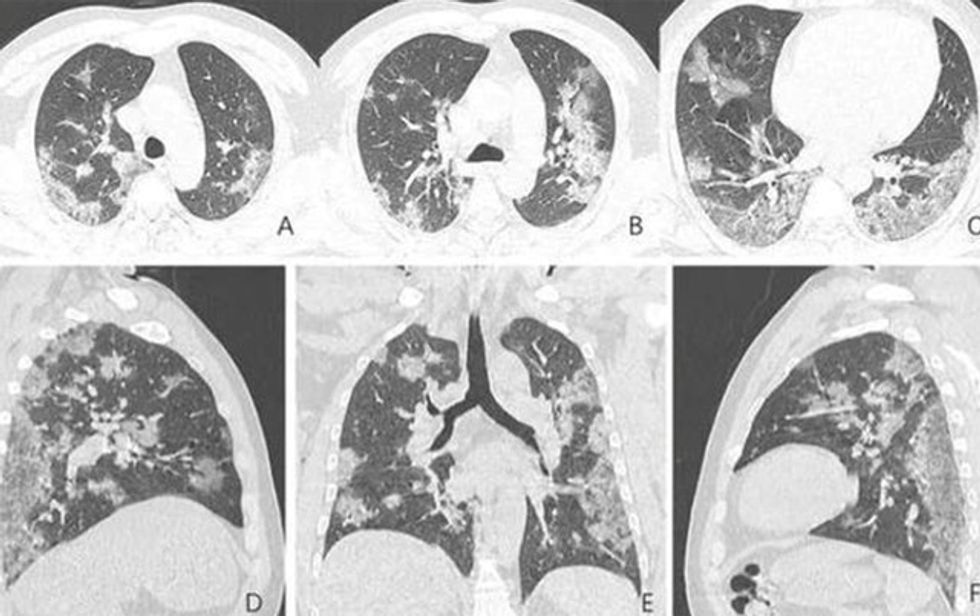

Imazhe të mushkërive në radiogramet e pacientëve të sëmurë me COVID -19